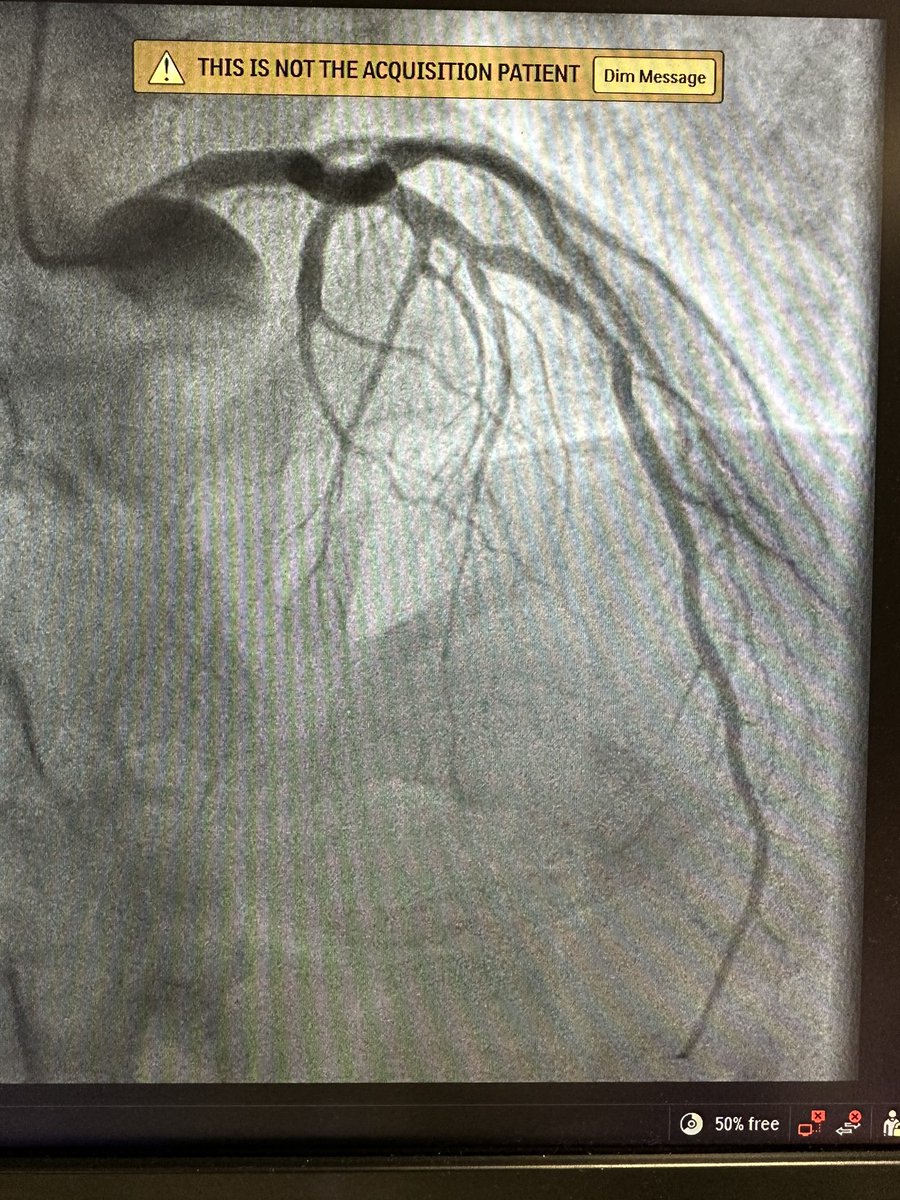

@SamanthaWasnie1 @drsoliscardio @BelenDiazAnton @sofiaglizarbe @migonzalezhoyo @PatonRubio @LuciaFGasso @HMHOSPITALES Maybe D1 is not D1, It is the intermediate branch and D2 is D1. Maybe.